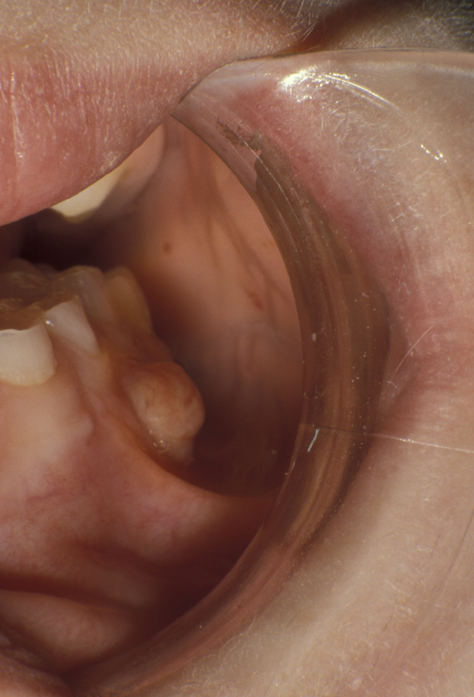

An abscess may remain localised and drain via a small intraoral sinus (a ‘gum boil’, see Figure 1) or may spread giving rise to a severe cellulitis involving multiple tissue spaces (a cervicofacial abscess, see Figure 2).

Figure 2: A CT scan showing a collection in the sub-masseteric space (between the lower jaw bone and the masseter muscle), one of the fascial spaces.